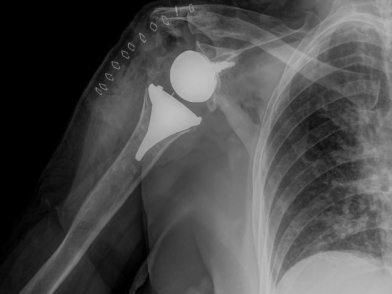

Η χειρουργική θεραπεία της αρθρίτιδας του ώμου συνιστάται σε μια ποικιλία διαφορετικών τεχνικών, οι οποίες μπορούν να εφαρμοστούν μετά από προσεκτική επιλογή ασθενών. Σε περιπτώσεις ήπιας προς μέτριας αρθρίτιδας με ελάχιστες οστικές μεταβολές, όπου τα συντηρητικά μέτρα δεν αποδείχθηκαν χρήσιμα, ο αρθροσκοπικός καθαρισμός της άρθρωσης αποτελεί μια εφικτή επιλογή για να “κερδηθεί χρόνος” πριν από μια επέμβαση αρθροπλαστικής. Στους νεότερους ασθενείς ιδιαίτερα, μπορεί να συνοδευτεί και από την αφαίρεση του υπερτροφικού αρθρικού υμένα, οστεοφύτων ή ελεύθερων ενδαρθρικών σωμάτων καθώς και θυλακοτομές, διαμορφώνοντας αυτό που είναι γνωστό ως ολοκληρωμένη αρθροσκοπική αντιμετώπιση (Comprehensive Arthroscopic Management – CAM). Ωστόσο, όταν έχουν εγκατασταθεί προχωρημένες αρθριτιδικές αλλοιώσεις, τότε η ενδεδειγμένη προσέγγιση είναι η αρθροπλαστική. Εφόσον οι μυς του στροφικού πετάλου και ο δελτοειδής παραμένουν ακέραιοι και λειτουργικοί, η προτιμώμενη τεχνική είναι αυτή της ανατομικής ολικής αρθροπλαστικής ώμου (anatomic Total Shoulder Arthroplasty – TSA), ενώ στην περίπτωση που το στροφικό πέταλο είναι ανεπαρκές, ενώ παραμένει λειτουργικός ο δελτοειδής, προτιμάται η ανάστροφη αρθροπλαστική ώμου (Reverse Shoulder Arthroplasty – RSA). Σε νεότερους ασθενείς και σε επιλεγμένες περιπτώσεις οστεονέκρωσης και ρευματοειδούς αρθρίτιδας με ανεπαρκές οστικό υπόβαθρο της ωμογλήνης, μπορεί να χρησιμοποιηθεί η ημιαρθροπλαστική του ώμου. Τέλος, σε περιπτώσεις επίμονης και ανθεκτικής λοίμωξης, νευρικής παράλυσης, σημαντικής ανεπάρκειας μαλακών μορίων ή υποτροπιάζουσας αστάθειας μετά από άλλες χειρουργικές παρεμβάσεις, η μόνη εφικτή επιλογή είναι η αρθρόδεση του ώμου, μια σπάνια χρησιμοποιούμενη τεχνική, η οποία ουσιαστικά εξαλείφει την κίνηση του ώμου και ακινητοποιεί την άρθρωση σε μια κατά το δυνατόν περισσότερο λειτουργική για τον ασθενή θέση, ώστε να χρησιμοποιεί τις υπόλοιπες αρθρώσεις του άνω άκρου.